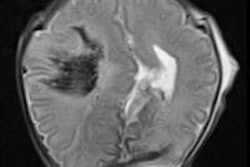

Consensus is growing that postmortem MRI is an effective, less invasive way of gathering information about fetuses compared with conventional autopsy. In a new study, U.K. researchers found that postmortem MRI can provide clinically important information in more than half of cases in which a conventional autopsy is nondiagnostic.

This approach has "significant implications" for future clinical practice, according to the authors. Read more.